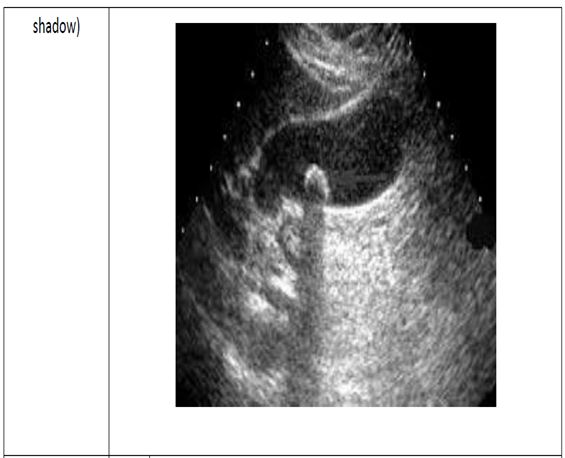

70.氣膽(pneumobilia)在超音波影像中,最可能有下列何者?

(A)後方回音增強(posterior acoustic enhancement)

(B)多重回音假影(reverberation artifact)

(C)音波陰影(acoustic shadowing)

(D)低回音(low echogeneity)